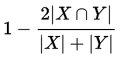

(1).Dice 损失

训练分割网络,我们采用 Dice Loss作为损失函数,Dice Loss定义如下:

Dice 系数是一种集合相似度函数,用来评判两个样本之间的相似程度,两个样本相似度越好,Dice系数越大,相应的损失就越小,故可采用1-Dice作为损失。